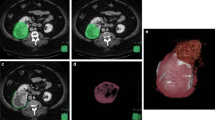

To assess the performance of computed tomography (CT) texture analysis to predict the presence of adherent perinephric fat (APF).

Seventy patients with small renal tumors treated with robot-assisted partial nephrectomy were included. Patients were divided into two groups according to the presence of APF. We extracted 15 image features from unenhanced CT and contrast-enhanced CT corresponding to first-order and second-order Haralick textural features. Predictors of APF were evaluated by univariable and multivariable analysis. Receiver operating characteristic (ROC) analysis was performed and the area under the ROC curve (AUC) to predict APF was calculated for the independent predictors.

APF was observed in 26 patients (37%). We identified entropy (p = 0.01), sum entropy (p = 0.02) and difference entropy (p = 0.05) as significant independent predictors of APF. In the portal phase, we identified correlation (p = 0.03), inverse difference moment (p = 0.01), sum entropy (p = 0.02), entropy (p = 0.01), difference variance (p = 0.04) and difference entropy (p = 0.02) as significant independent predictors of APF. Combining these parameters yielded to an ROC-AUC of 0.82 (95% CI 0.65–0.86).

Results from this preliminary study suggest that CT texture analysis might be a promising quantitative imaging tool that helps urologist to identify APF.